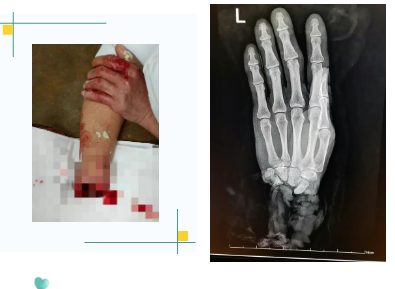

患者为48岁食品厂工人,在操作机器时不慎被搅面机绞伤,导致右手腕完全离断。赶到医院时,陪同人员怀中的毛巾里,一只沾满面粉、苍白干瘪的手掌令医护人员着实揪心:断端处肌腱、血管与神经缠绕,血迹已凝固。

手术中,主刀医生在显微镜下精细操作:清创、探查、骨折固定……每一步都关乎着手掌能否“复活”。真正的挑战出现在血管吻合阶段——患者前臂尺动脉、桡动脉因严重挤压全部断裂,内膜损伤广泛,直接吻合后血流无法恢复。关键时刻,张辉医生果断决定施行“静脉移植术”,从患者前臂截取一段健康静脉,桥接在断裂的动脉之间。

晚22:40,随着最后一针缝合完成,移植的静脉逐渐泛起红润——血流恢复了!离体十余小时的右手手指慢慢显现血色,指腹逐渐饱满。手术室外,家属紧紧握住医护人员的手,泪水夺眶而出:“谢谢你们,真的谢谢……”

术后,患者生命体征平稳,再植手掌血运良好,末梢红润,标志着再植手术获得成功。据医疗团队介绍,患者病情稳定后,预计功能恢复将是一个长期过程,可能需要一年以上时间。